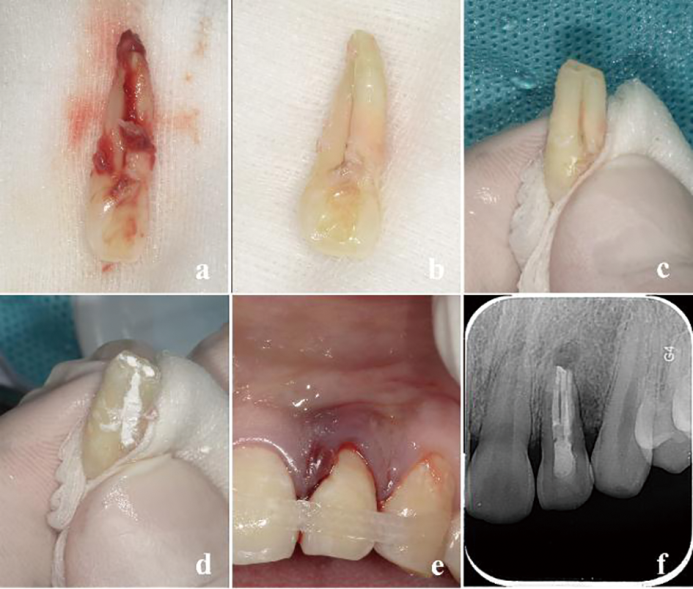

显微根管治疗结合意向性牙再植术治疗双根管上颌侧切牙畸形根面沟1例

Microscopic root canal therapy combined with intentional replantation for the treatment of palatogingival groove in the maxillary lateral incisor with two root canals: A case report

畸形根面沟(palatogingival groove,PGG)是一种位于根面的发育性解剖异常,多见于上颌侧切牙。PGG处牙周组织附着薄弱,易滞留菌斑,引起局部牙周炎症,感染可通过根面沟扩散至牙髓组织,最终导致牙周牙髓联合病变。本文报道了1例因畸形根面沟引起的左上颌侧切牙牙周牙髓联合病变,经显微根管治疗联合意向性牙再植术成功保留患牙,并进行文献回顾,探讨了PGG的诊断要点及治疗方案。

Palatogingival groove (PGG) is a developmental anatomical defect located on the lingual root surface, frequently observed in maxillary lateral incisors. The periodontal attachment in this region is delicate, which makes it vulnerable to plaque accumulation and increases the risk of periodontal inflammation, leading to combined periodontal-endodontic lesions. This article reports a case of a combined periodontal-endodontic lesion in a left maxillary lateral incisor caused by PGG. The tooth was successfully preserved through microscopic root canal therapy combined with intentional replantation. Additionally, a literature review was performed to highlight the key diagnostic features and treatment strategies for PGG.